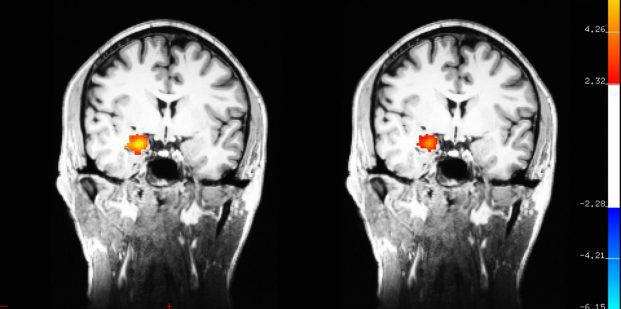

دزبوردز در پژوهش خود از fMRI بهره گرفت که با این روش نه تنها عکس هایی از مغز تهیه کرد بلکه گزارشات رخداد فعالیت مغزی طی اسکن نیز ثبت گردید. در سال ۲۰۱۲ او شرح داد که تغییرات در فعالیت مغز در افراد مورد آزمایش که مراقبه را فراگرفته بودند حتی هنگامی که آن ها در حال مراقبه نبودند، به طور ثابت حفظ شده بود. دزبوردز، اسکن هایی از قبل و بعد مغز افراد مورد آزمایش که مراقبه را طی یک دوره دو ماهه فراگرفته بودند، تهیه کرد.او این اسکن ها را نه تنها در زمان مراقبه بلکه زمانی که کیس های مورد مطالعه در حال انجام کارهای روزمره خود بودند نیز تهیه کرد.

با این حال در اسکن ها هنوز تغییرات درالگوهای فعالیت های مغزی نمونه های مورد آزمایش از ابتدا تا آخر مطالعه قابل تشخیص بود، اولین بار چنین تغییری در بخشی از مغز به نام آمیگدال شناسایی شد.

او در کار اخیر خود در حال بررسی اثرات مراقبه بر روی مغز افرادی است که از نظربالینی به افسردگی مبتلاهستند، گروهی که مطالعات نشان داده اند مراقبه بر روی آن ها موثر است. دزبوردز در حال تهیه و بررسی اسکن های fMRI قبل و بعد یک دوره ی هشت هفته ای دوره شناخت درمانی مبتنی بر ذهن آگاهی [MBCT[2 در گروهی است که توسط شاپرو غربال و انتخاب شده اند.

محققان سرعت دست کشیدن افراد از افکار منفی (یک عمل دشوار در افراد مبتلا به افسردگی)را اندازه گیری خواهند کرد. فرایند برای یک گروه کنترل نیز تکرار خواهد شد که این گروه تحت تمرین، ریلکس کردن عضلانی و آموزش درمورد افسردگی به جای MBCT قرار گرفته اند. درحالی که امکان پذیر است که در بیماران در گروه کنترل همچنین علائم افسرده کننده کاهش یابد. نظر دزبوردزاین است  تفاوتی که ممکن است در اسکن ها آشکارشود ، باید درطی مکانیسم های مختلف در مغز رخ دهد. این کار که بودجه ی مرکز ملی سلامت تکمیلی و یکپارچه را دریافت کرد، از سال ۲۰۱۴ در دست بحث است و مورد انتظار است که در سال ۲۰۱۹ به پایان برسد.